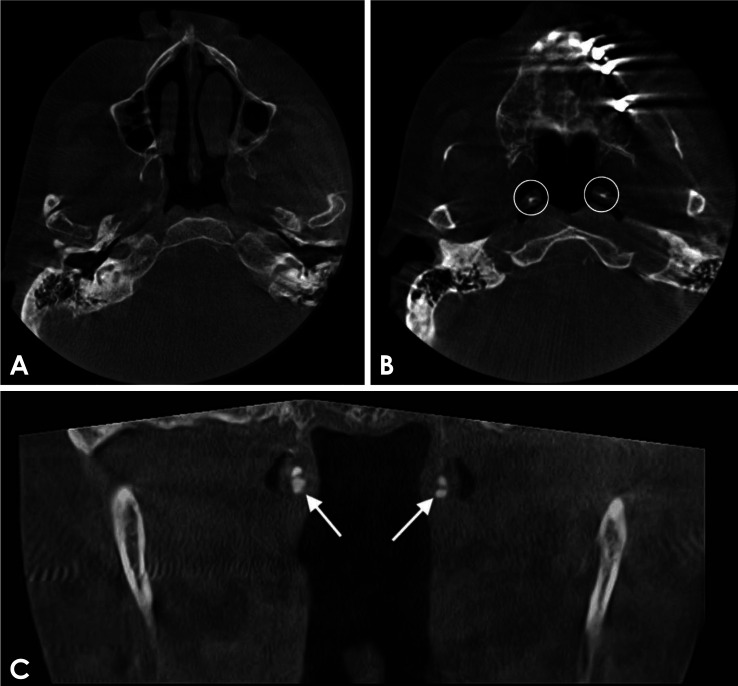

作者在本文中介绍了一例不寻常的病例,患者的咽鼓管钙化在全景图像上被伪装成颞下颌关节的松动放射斑,这给诊断带来了挑战。患者是一名 72 岁的女性,为改善咀嚼功能到牙科接受种植治疗。经口腔颌面放射医师委员会认证,该患者接受了锥形束计算机断层扫描。扫描结果显示,颞下颌关节没有钙化迹象;但双侧咽鼓管软骨部分发现结节状钙化。此外,本报告还简要回顾了颞下颌关节钙化松散体的鉴别诊断,并提供了需要定期加强的信息。

The author herein presents an unusual case of eustachian tube calcification masquerading as loose radiopacities in the temporomandibular joints on a panoramic image, creating a diagnostic challenge. The patient, a 72-year-old woman, presented to the dental service for implant treatment to improve her masticatory function. A cone-beam computed tomography scan was performed and reviewed by a board-certified oral and maxillofacial radiologist. The scan showed no evidence of calcifications in the temporomandibular joints; however, it revealed nodular calcifications within the cartilaginous portion of the eustachian tube bilaterally. Additionally, this report briefly reviews the differential diagnosis of calcified loose bodies in the temporomandibular joint and provides information that needs to be reinforced periodically.